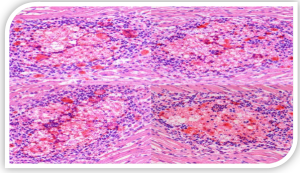

یافتههای میکروسکوپی: مهمترین ضایعه میکروسکوپی، حضور اجسام بازوفیلیک داخل هستهای در سلولهای کبدی (هپاتوسیتها) است . نکروز انعقادی

چندکانونی در کبد، دژنرسانس و نکروز سلولهای عضله قلب و توبولهای کلیوی نیز از دیگر یافتههای بافتشناسی هستند.

تشخیص اولیه بر اساس مشاهده علائم بالینی و ضایعات مشخص کالبدگشایی بهویژه آبآوردگی پریکارد و هپاتیت همراه با اجسام بازوفیلیک داخل هستهای در بررسیهای میکروسکوپی بافت کبد صورت میگیرد .